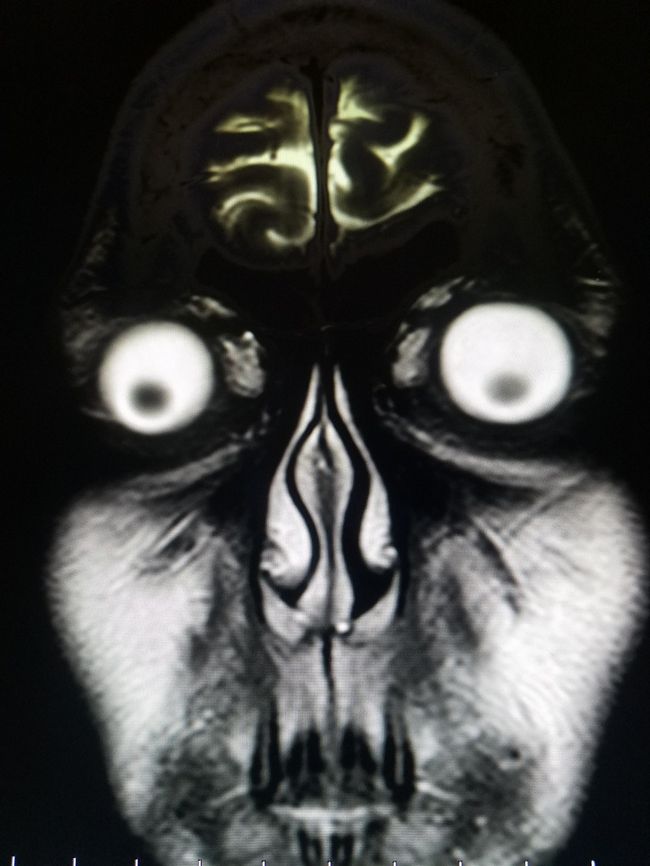

9 – Isso é assustador